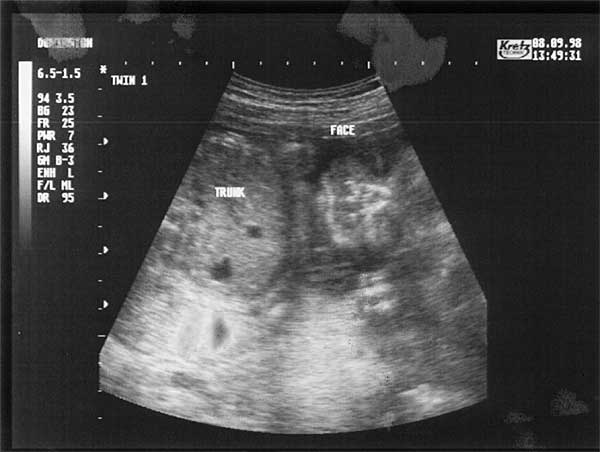

24 Weeks - Tuesday 8th September 1998.

Twenty Four Week Scan 2